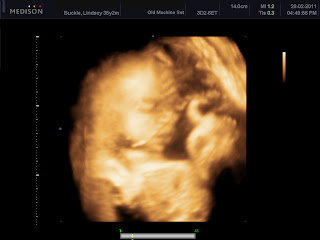

Well, I'm going to finish by sharing some fuzzy 3D images of our new baby's face. The cord was in front so it was a bit hard to get a nice clean image. Go on then, knock yourselves out wondering whether it's a boy or a girl and who it looks like.